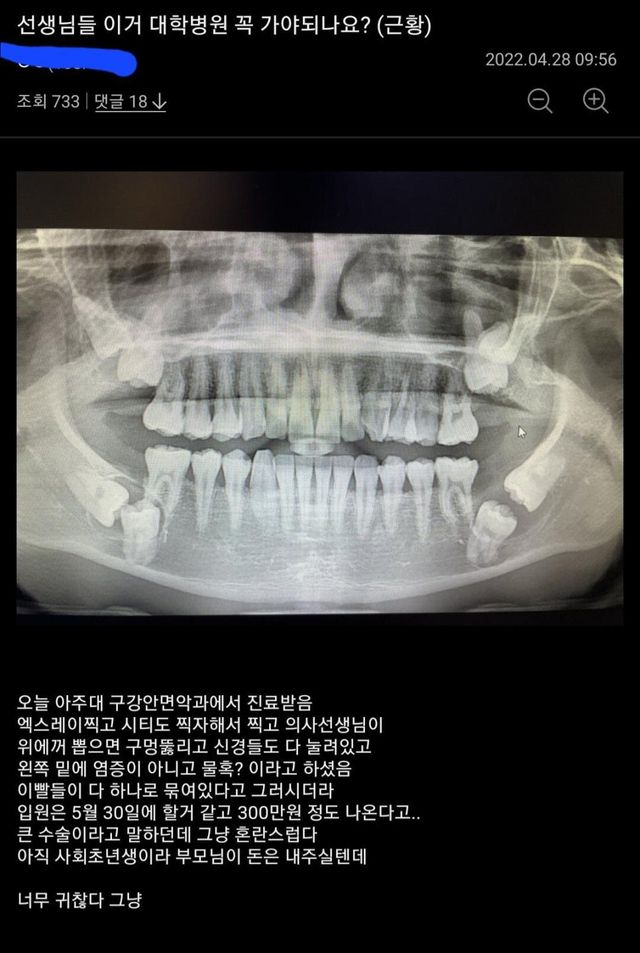

전생에 뭘 했길래사랑니가 저렇게 나?